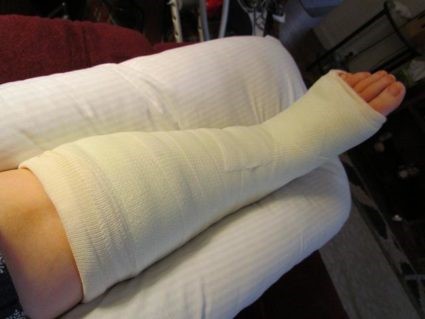

- Наложение гипсовой повязки, начиная от пальцев ступни и заканчивая верхней третью голени (если перелом не сопровождается смещением).

Устранить переломовывих кости можно только оперативно. Но даже такой метод лечения будет крайне затруднителен. Как только вывих вправлен и проведена точная репозиция отломков, зону перелома фиксируют специальными спицами. Репозиция может быть затруднена, если угол поворота тела кости – более 90°. Спустя один месяц проводят удаление спиц, замену наружного гипса, который теперь накладывают вплоть до колена. Гипс при этом содержит вмонтированный металлический супинатор.

Снимать гипс можно примерно через 3 месяца. Чтобы избежать развития асептического некроза кости, дозированные нагрузки на ногу разрешены не ранее, чем на 9 неделе после проведения операции, а полная нагрузка – не ранее 5 месяцев.